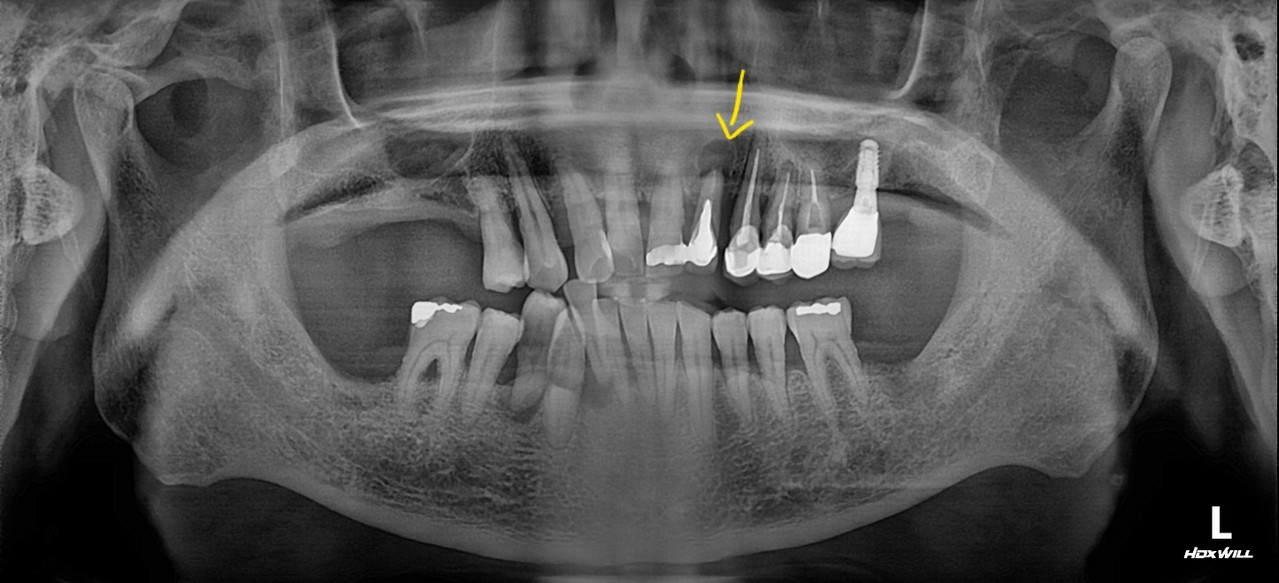

Stage 3

Pulpitis (Nerve Infection)

Bacteria have reached the dental pulp causing severe pain

Root canal treatment followed by a crown

We offer same-day fabrication of all-ceramic and zirconia crowns

Stage 4

Apical Periodontitis

/ Cyst Formation

Infection has spread to the root tip, causing swelling or pus formation

Extraction and implant placement may be necessary

Retreatment of root canal or surgical intervention may be required